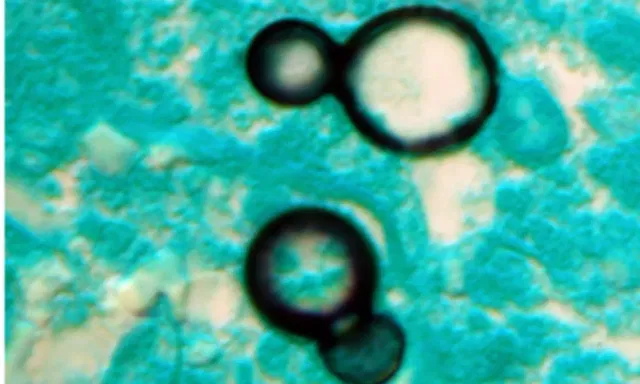

NEW DELHI: Including fungal pathogens is crucial in the fight against deadly antimicrobial resistance, which is rapidly becoming a public health threat worldwide, according to a study published in The Lancet journal on Friday.

The study, led by scientists at the universities of Manchester in the UK, Amsterdam, and the Westerdijk Institute in the Netherlands, showed that most fungal pathogens identified by the World Health Organisation (WHO) are either already resistant or rapidly acquiring resistance to antifungal drugs.

These fungal pathogens account for around 3.8 million deaths a year.

Aspergillus, Candida, Nakaseomyces glabratus, and Trichophyton indotineae are the major fungicide resistant infections. These can have devastating health impacts on the elderly and people with weak immune systems.